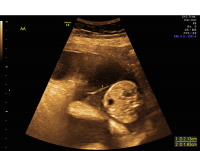

Twin-Twin Transfusion Syndrome stuck twin

Beginning at about 16 to 18 weeks of pregnancy, all MCDA twins undergo regular ultrasound surveillance for TTTS. If excess fluid (polyhydramnios) is noted for one twin and decreased fluid (oligohydramnios) is observed for the other, then a diagnosis of TTTS is confirmed and the health of the twins is further evaluated. While a range of options exist for the management of TTTS, contemporary therapy for early-onset, advanced-stage TTTS ideally involves fetoscopic laser therapy. Pregnancies complicated by TTTS require close surveillance even after therapy, and are at high risk for premature delivery.